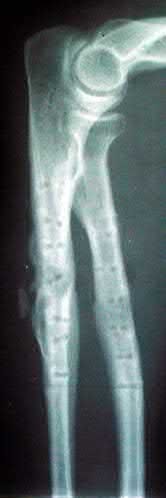

Figure A shows an AP radiograph of a both bone forearm fracture. Figure B shows an AP and lateral radiograph of an atrophic non-union of the ulnar shaft. Illustration A shows a lateral x-ray of a fully healed radius and ulna after hardware removal 1 year after revision surgery.